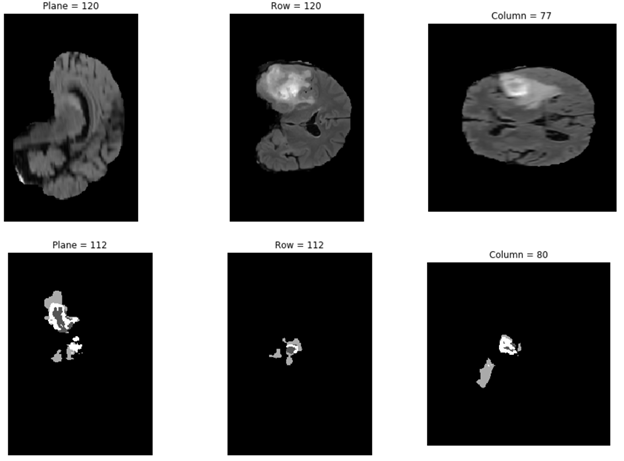

다음의 세 가지 셀을 실행하면 pip 인스톨로 니바벨을 설치하고, 데이터세트에서 이미지를 선택한 다음, 매트플롯라이브러리(matplotlib)로 데이터세트에서 골라낸 제3의 이미지를 플로팅(plotting)할 수 있습니다. 코드의 이미지 주소를 변경하여 다른 데이터세트의 이미지들도 확인이 가능합니다.

img_arr = nib.load('/data/MICCAI_BraTS_2019_Data_Training/HGG/BraTS19_2013_10_1/BraTS19_2013_10_1_flair.nii.gz').get_data()

(n_plane, n_row, n_col) = img_arr.shape

_, (a, b, c) = plt.subplots(ncols=3, figsize=(15, 5))

show_plane(a, img_arr[n_plane // 2], title=f'Plane = {n_plane // 2}')

show_plane(b, img_arr[:, n_row // 2, :], title=f'Row = {n_row // 2}')

show_plane(c, img_arr[:, :, n_col // 2], title=f'Column = {n_col // 2}')

결과는 Figure 4와 유사한 형태로 얻어집니다.